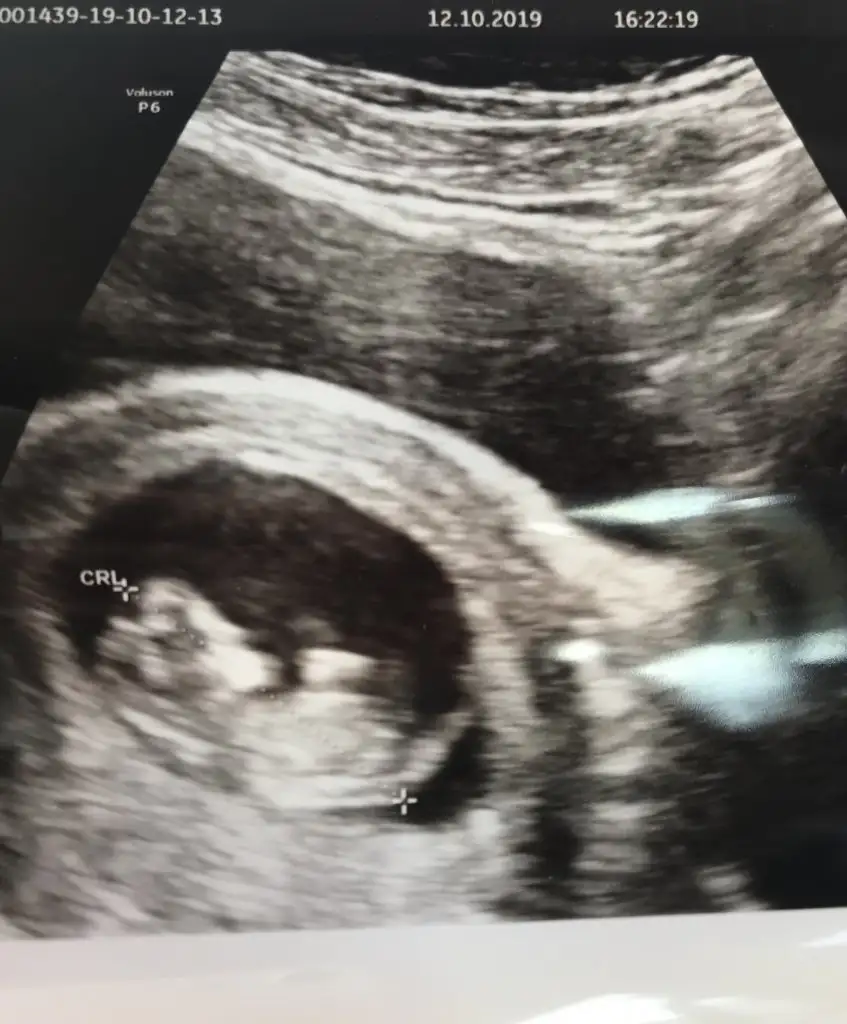

saglıkla gelsin prensesIkra Meyra merhaba cinsiyeti öğrendik kızımız olacakmışBu da son ultrason fotoğrafımız 13 haftalık

Biliyorum erken ama sabirsizim şuan 8+4Tahminim neydisaglıkla gelsin prenses